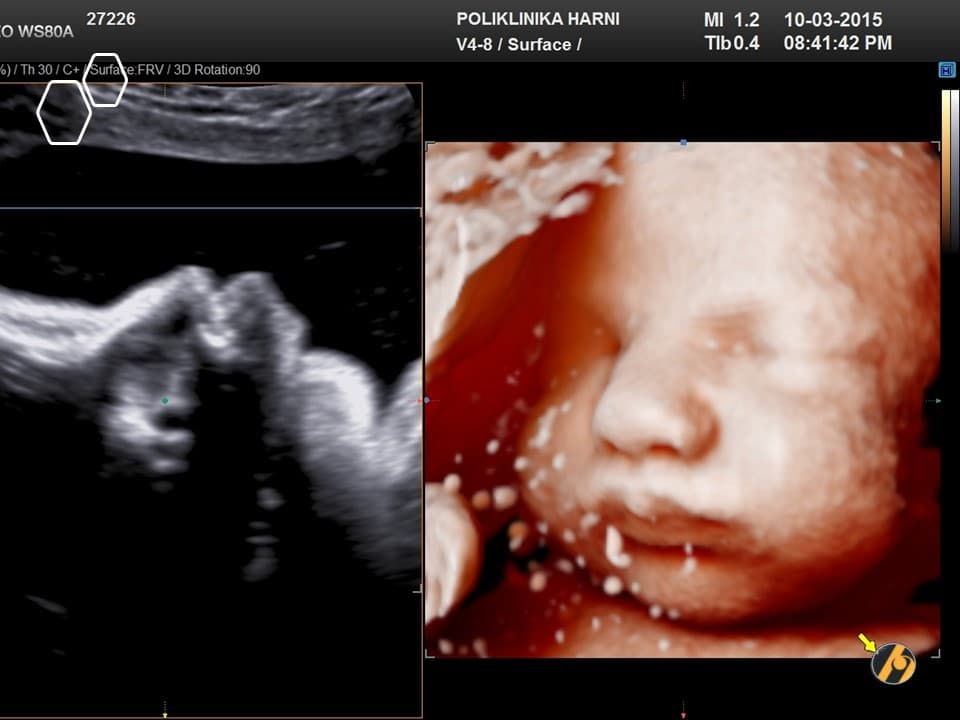

U 39. tjednu trudnoće beba je potpuno razvijena i spremna za život izvan maternice.

Prosječna duljina bebe iznosi oko 50 centimetara, a težina se obično kreće između 3200 i 3600 grama, iako su moguće individualne razlike. Potkožno masno tkivo sada je dobro razvijeno i pomaže bebi u održavanju tjelesne temperature nakon rođenja.

Pluća su u ovoj fazi funkcionalno zrela, dok mozak i živčani sustav nastavljaju sazrijevati i nakon rođenja. Beba ima razvijen refleks sisanja i hvatanja koji će joj omogućiti hranjenje majčinim mlijekom i prve interakcije s roditeljima.

Većina beba sada je u položaju glavom prema dolje, što je najpovoljniji položaj za vaginalni porod. Prostor u maternici postaje vrlo ograničen pa su pokreti drukčiji nego ranije u trudnoći. Oni su sporiji, ali često snažni i jasno osjetljivi.